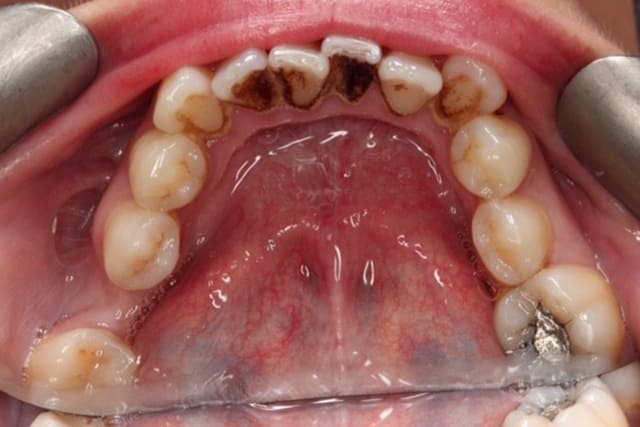

Dental Hygienist service before image – Bayswater Dental Clinic